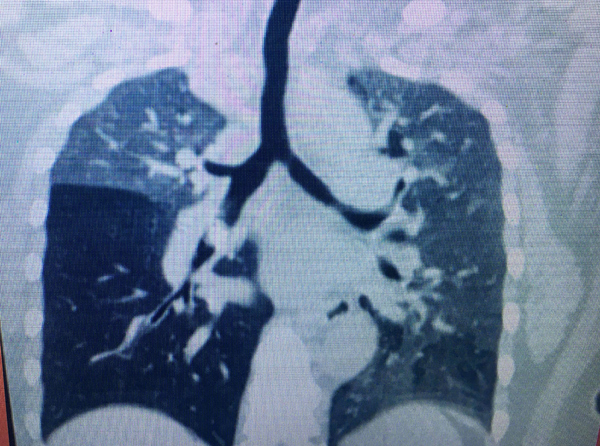

Tại Bệnh viện Tai-Mũi-Họng TP.HCM, bệnh nhân được chỉ định chụp CT scan phổi và phát hiện dị vật phế quản thùy trung gian phổi phải; viêm phổi thùy giữa; thùy dưới phải nên cho nhập viện.

“Các trường hợp dị vật đường thở không thể thấy trên phim phổi bình thường, đây là nguyên nhân khiến mảnh xương vịt bị bỏ quên trong đường thở bệnh nhân gần năm trời. Đối với những trường hợp này, theo BS Thủy, chỉ có chụp CT scan hoặc nội soi ống mềm, ống cứng thì mới phát hiện được”, BS Thủy lưu ý.